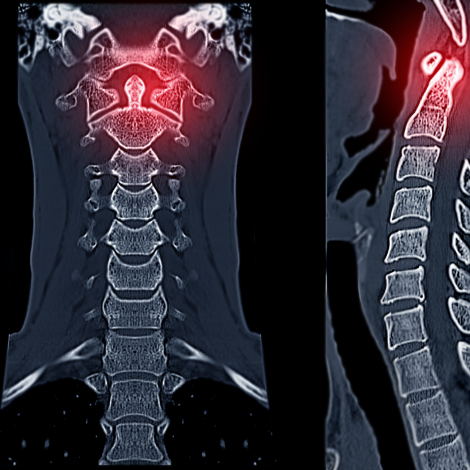

Neck CT

CT of the neck is a study of the neck region from the skull base (bottom of the head) to the lung apices (top of the chest). There are a variety of indications for this study, based on the structure or pathology of interest. These include (but are not limited to): Parotid or submandibular gland lesion or infection; head and neck cancers; pharyngeal/retropharyngeal or tonsillar abscess; neck mass or abscess; tongue mass or lesion; foreign body in the neck or upper airway; tumors or infections involving the vocal cords.